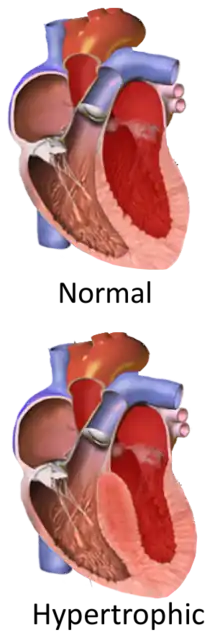

Hypertrophic cardiomyopathy (HCM) is a heart disease in which a portion of the heart becomes thickened without an obvious cause.[9] Symptoms vary from none to tiredness, leg swelling, and shortness of breath.[3] It may also result in chest pain or fainting.[3] Complications include heart failure, an irregular heartbeat, and sudden cardiac death.[4][5]

It is most commonly inherited from a person's parents.[7] It is often due to mutations in certain genes involved with making heart muscle proteins.[7] Other causes may include Fabry disease, Friedreich's ataxia, and certain medications such as tacrolimus.[6] It is a type of cardiomyopathy, a group of diseases that primarily affects the heart muscle.[4] The stiffened heart muscle results in the heart being less able to pump blood and the thickened interventricular septum can result in blocking the flow of blood from the left ventricle into the aorta and a weakened mitral valve.[2][9]